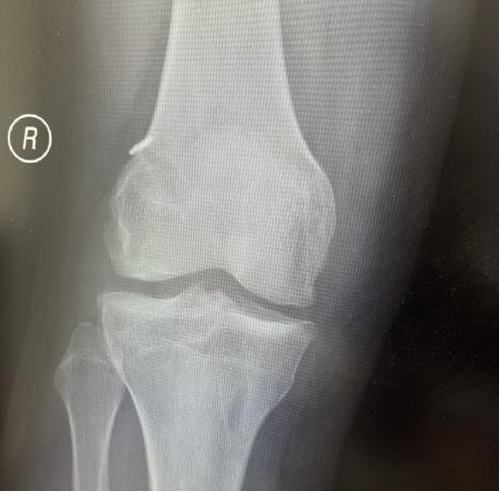

術(shù)后X線片